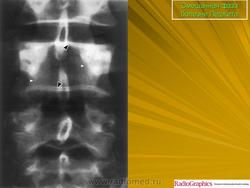

Литическая фаза.

Смешанная фаза.

Бластная фаза

Принято различать три фазы развития П. б.: очаговая интенсивная резорбция кости (остеолитическая, или деструктивная, фаза), смешанная фаза, когда наряду с рассасыванием кости идут процессы новообразования ее, и остеобластическая, или склеротическая, фаза с образованием типичных мозаичных структур.